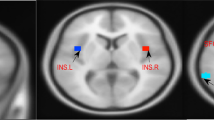

Alterations of ALFF in ID patients

Compared with HCs, ID patients had significantly increased ALFF in the left insula (p = 0.036) and right amygdala (p = 0.039), as well as decreased ALFF in the right SPL (p = 0.005) at the threshold we set (cluster-level p < 0.05, FDR corrected) (Table 3; Fig. 2).

Cortical areas of increased/decreased ALFF in ID patients compared with HC. The red color shows increased spontaneous functional activity in the right amygdala and the left insula in ID patients. The bule color shows decreased spontaneous functional activity in the right superior parietal lobule in insomnia patients. SPL, superior parietal lobule; L, left; R, right

Alterations of seed-based FC in ID patients

The center points of the peak t value in brain regions that showed significant differences in ALFF between ID patients and HCs (left insula, right amygdala, and right SPL) were defined as spherical ROIs (r = 3 mm). The FC analysis revealed increased connectivity between the left insula and bilateral precentral (Table 4; Fig. 3) and increased connectivity between the right amygdala and left PCC in the ID patients (FDR correction, p < 0.05) (Table 4; Fig. 4). However, ID patients failed to reveal any suprathreshold clusters between the ROI of the right SPL and the whole brain regions.